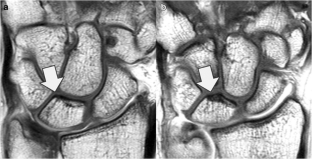

Fig. 1

Fig. 2

Fig. 3

Fig. 4

Fig. 5

Fig. 6

Fig. 7

Fig. 8